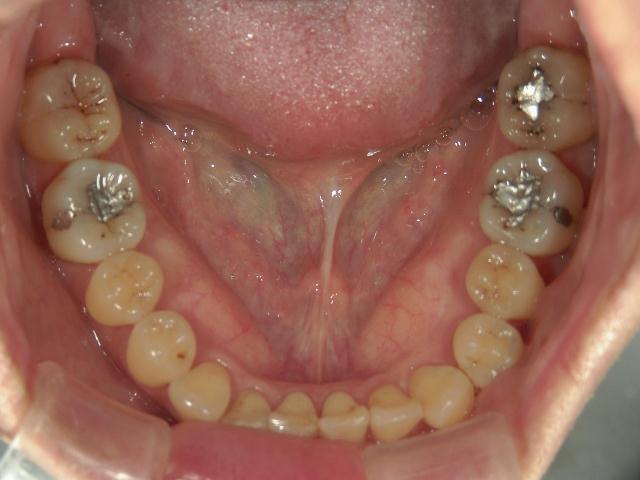

矯正歯科 治療前 下顎